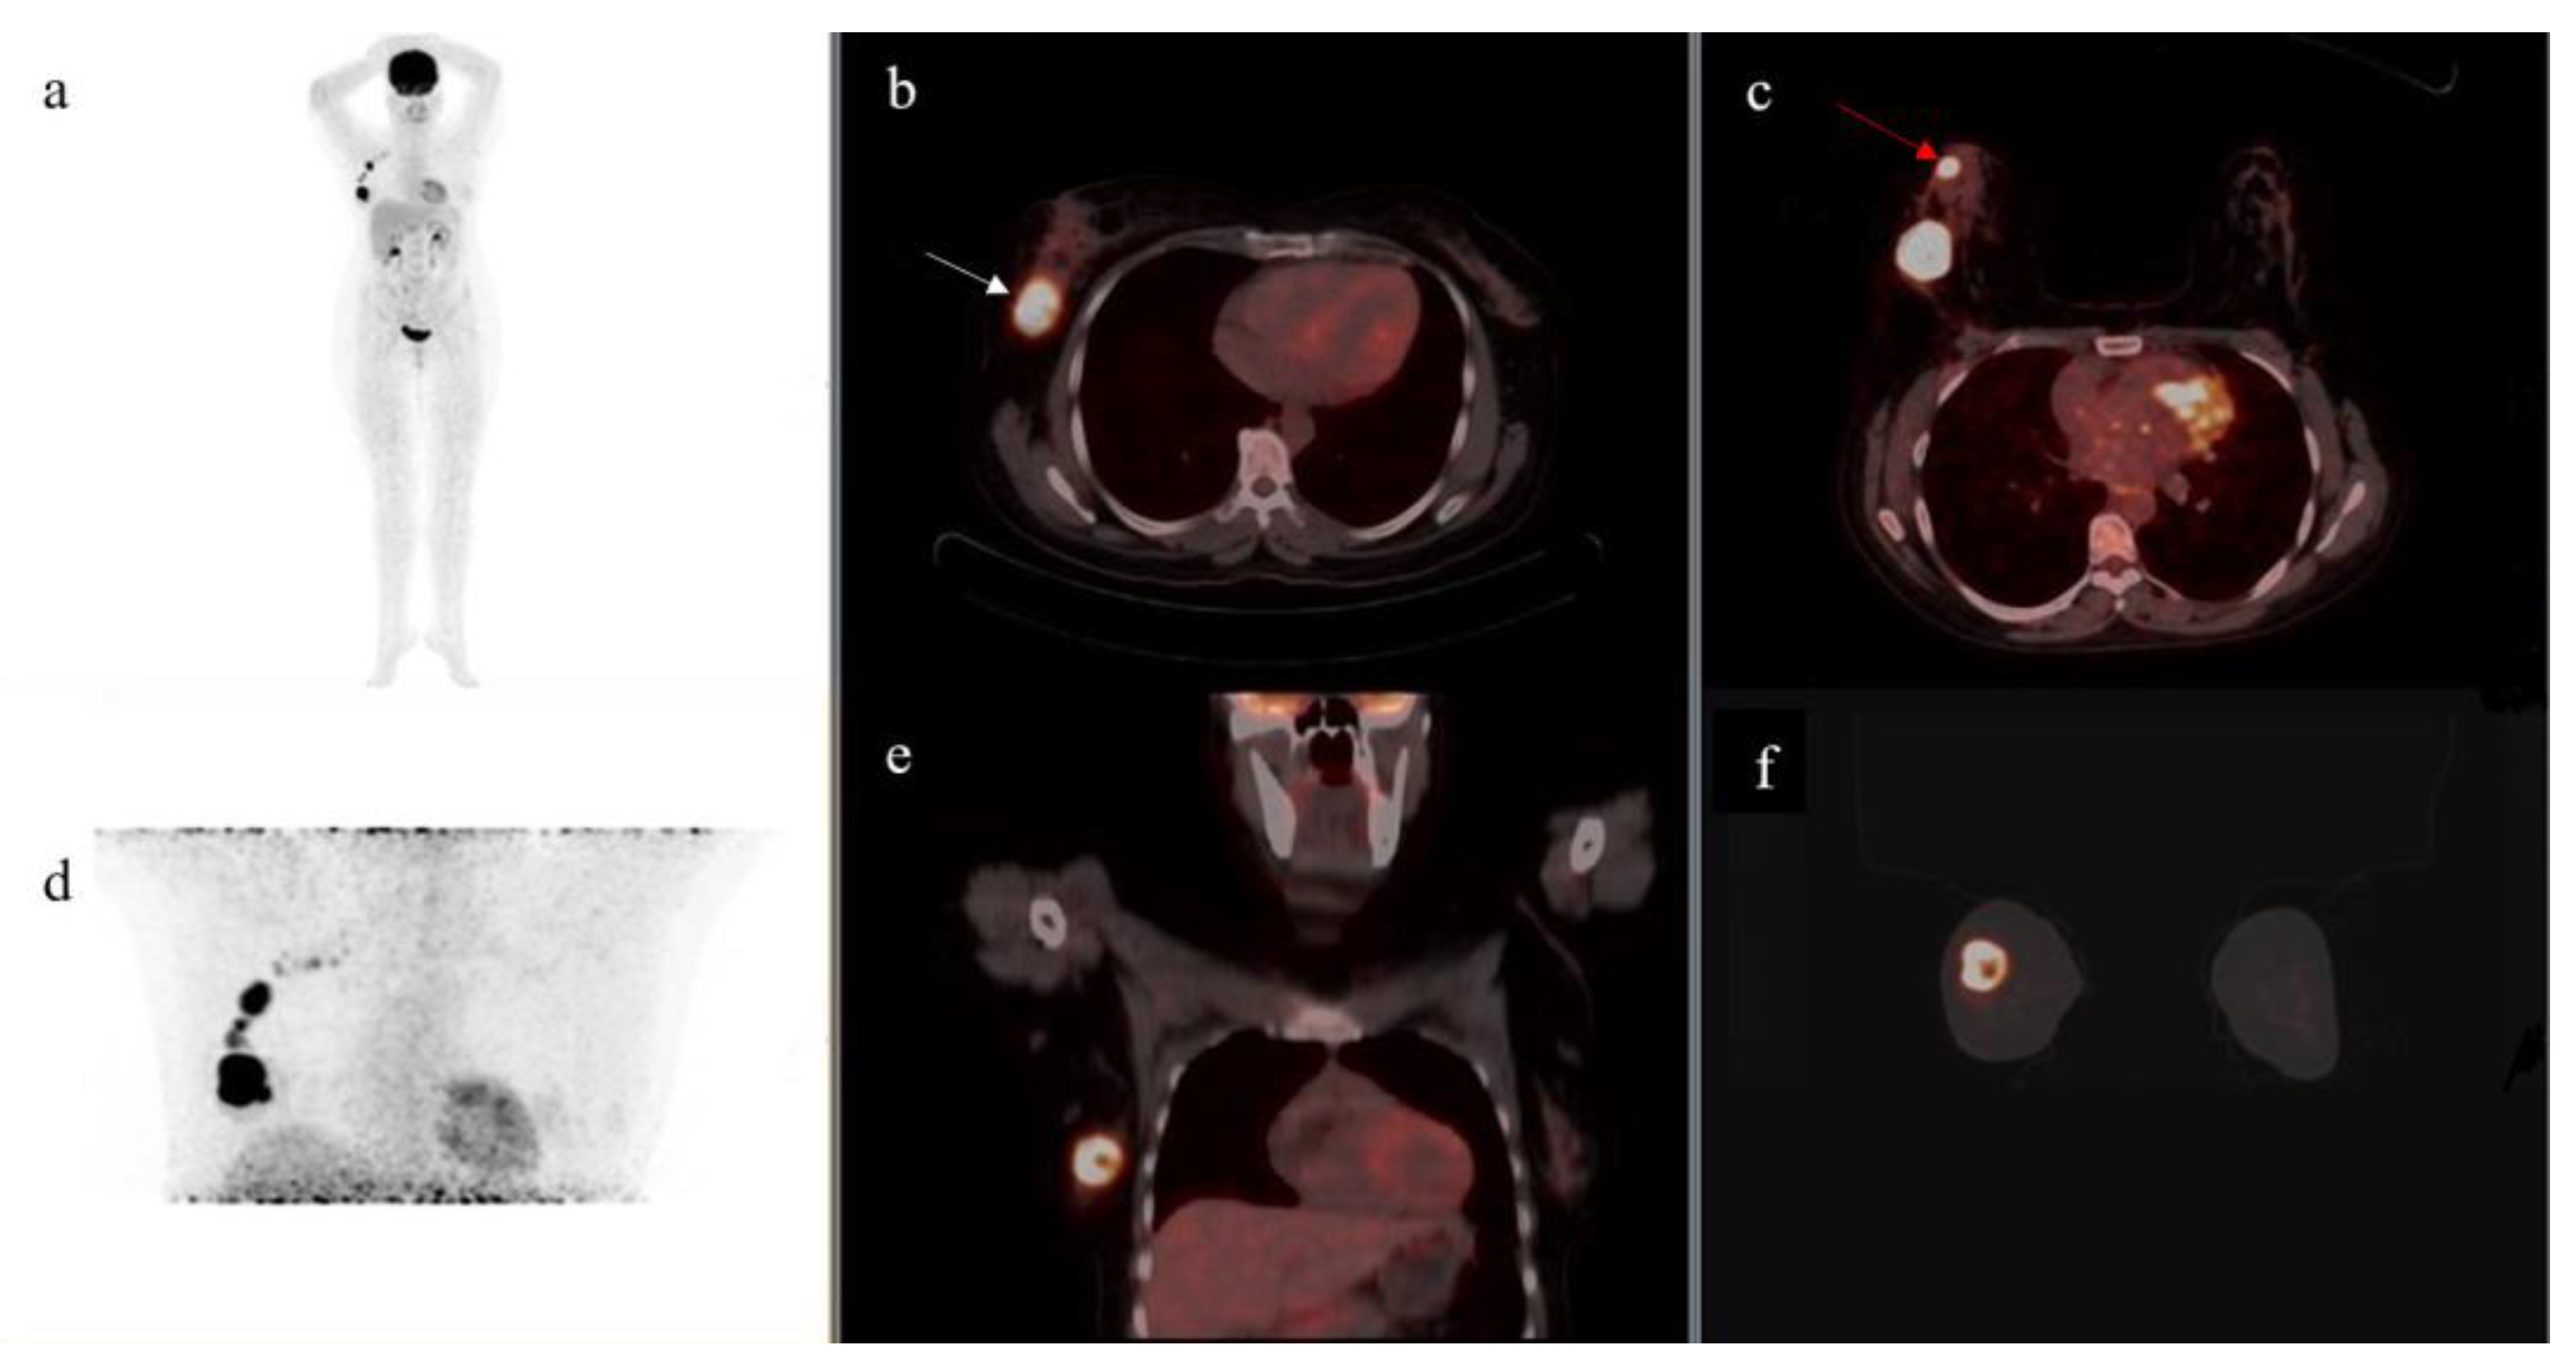

- On supine position acquisition, primary breast lesions were missed in three patients, all of which were detected on prone position. One such example is seen in Figure 2,